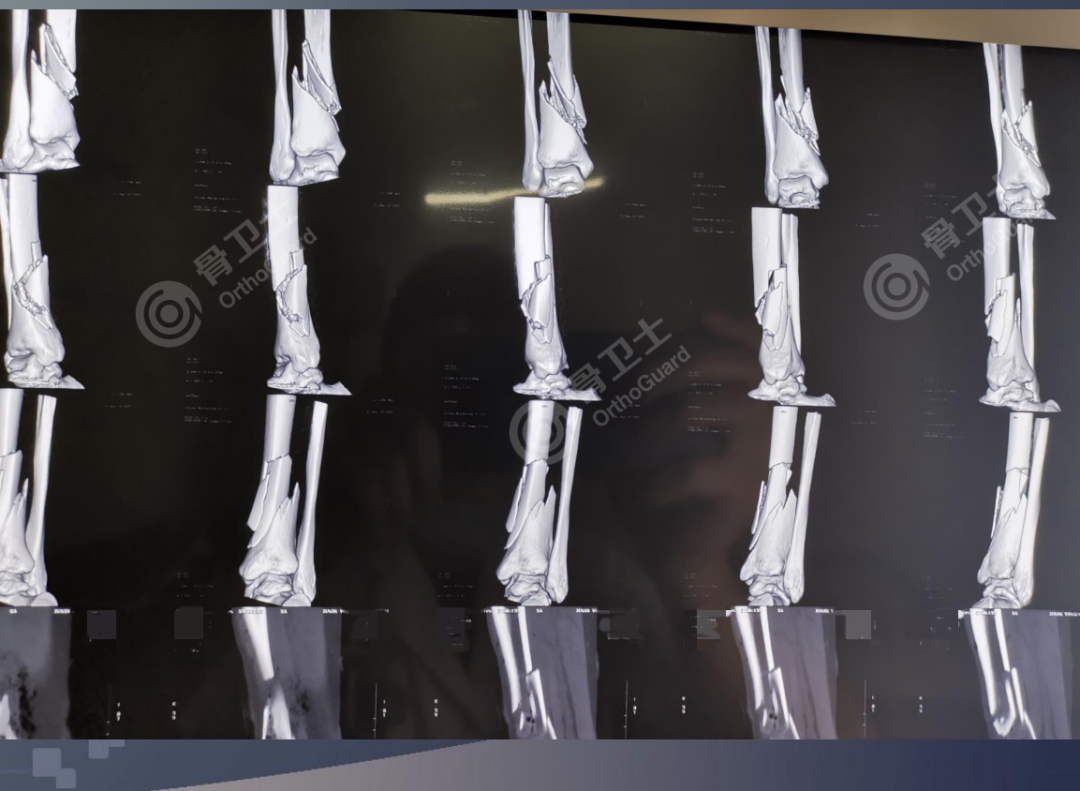

基本情况:女,56岁,因右小腿外伤后疼痛流血2小时入院。

查体:右侧小腿肿胀明显,右小腿中下端内侧见一直径约0.5cm皮肤伤口,流血,皮肤边缘整齐,污染轻,无张力性水泡,小腿中下1/3处及小腿上端外侧压痛明显,扪及骨擦感及异常活动,踝关节因疼痛活动受限,被动活动疼痛明显,无被动牵拉疼,足背动脉搏动正常,足趾感觉、活动正常。肢体远端血运未见异常。

诊断:右胫腓骨开放性骨折。

▲患者术前影像